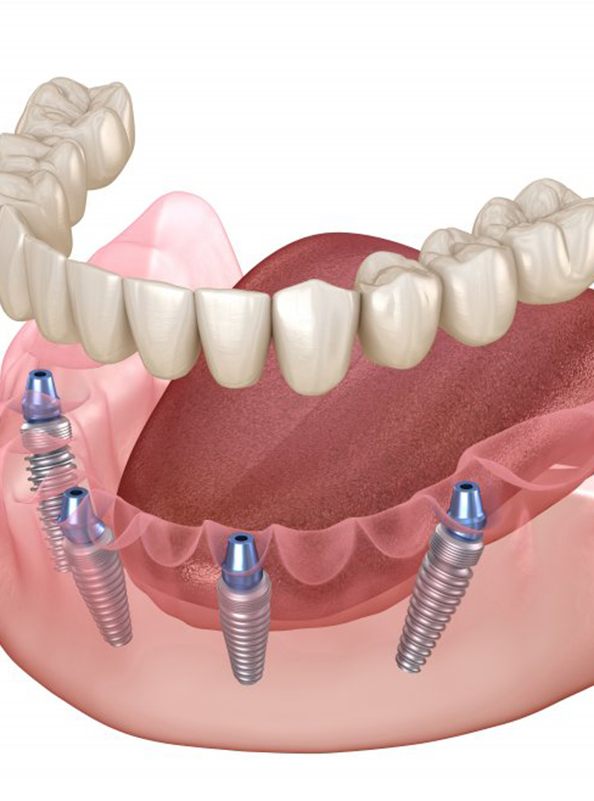

Dental implants are titanium posts surgically placed in and naturally fused with the jawbone to create the most reliable, durable, and lifelike tooth restoration available. However, these appliances require the jawbones to be thick enough to be placed, and All-on-4 can securely fasten a full denture to your gums using the fewest implants possible. To do this, four dental implants are placed at the thickest points of the jawbone. The two posts located in the rear of the mouth will be positioned at 45-degree angels to maximize their security and leverage. A lifelike denture will then be mounted on the implants with abutment pieces, resulting in a comfortable and reliable set of teeth that should never slide out of position.